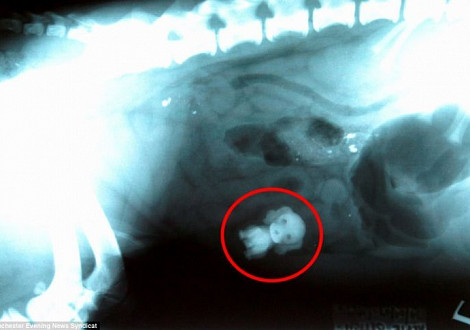

Небольшие предметы из пищевода извлекаются инструментами под местной анестезией. Наиболее точная диагностика наличия инородных тел в желудке и кишечнике животного возможна при проведении рентгенологического исследования.